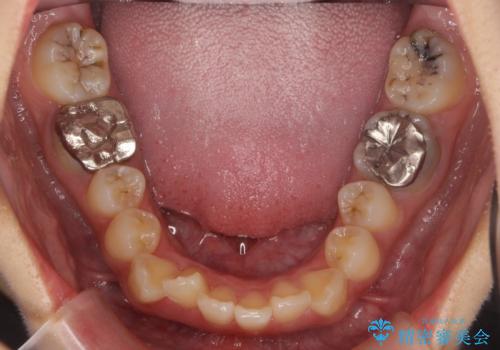

- 前歯のがたつきを主訴に来院。

保険治療の被せ物が前歯に2本あり、矯正治療で移動後にセラミックでやり替えを行っています。

右上のかみ合わせがずれていたため、インプラント矯正を行い、奥歯を後ろに下げて治療しています。